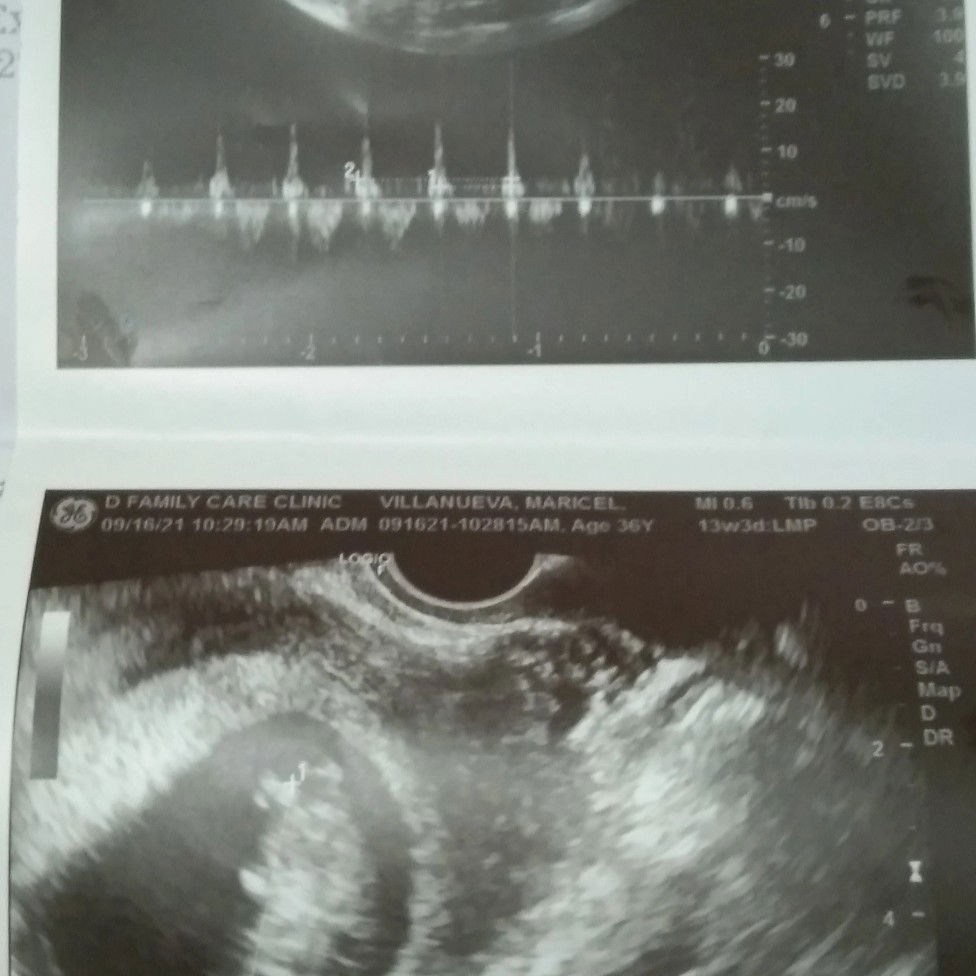

mga momshie, ask ko lang dapat b mag wory dhil wlang marinig na heartbeat sa baby ko?19 wiks preggy

yes regular Po Ang check up ko s OB.